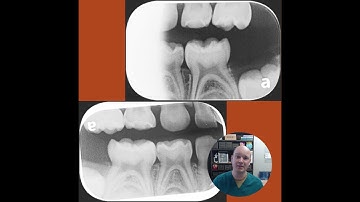

When SMART Isn't Enough: A Case Review on SDF Limitations and IV Sedation for Kids